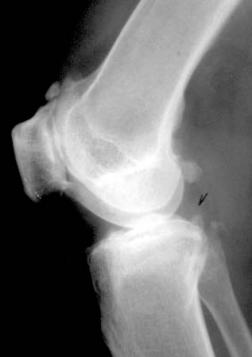

临床与病理:1、年龄:20-40岁,约65%;2、部位:长管状骨骨端,膝关节附近居多

3、病理: I级:良性;II级:潜在恶性;III级:恶性

X线表现:① 多数为偏心性骨破坏 (溶骨型)② 局部骨 膨胀性,骨皮质变薄形成薄层骨壳,无硬化边③ 大小不一的分隔小房呈肥皂泡状, 并见骨嵴。

④ 无骨膜反应,⑤一般不穿破关节软骨

CT:骨破坏区、骨壳、骨嵴、肿块

MRI: T1低或等、T2高信号,坏死囊变区T1较低T2明显高。肿瘤内出血T1高T2高;增强后可强化。;鉴别诊断 :骨囊肿、溶骨型骨肉瘤